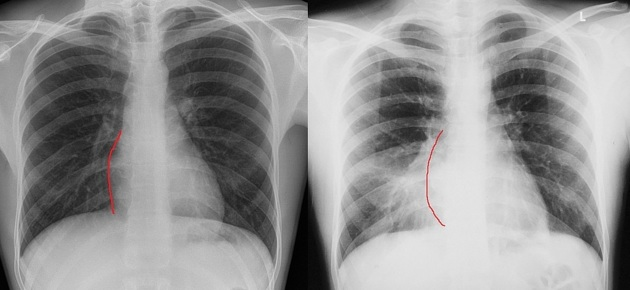

Which structure forms the patents right cardiac border?

what structure normally appears as a circle on the superior aspet of the cardiac silhouette in the AP chest radiograph

Transverse aortic arch or the aortic knob

What is another name for the aortic knob

Transverse aortic arch

When viewing the heart in LAO projection what structures form the right cardiac border

Right atrium and right ventricle.